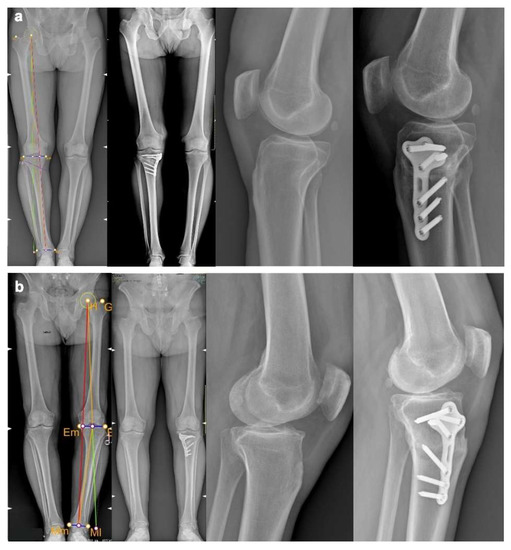

4.4. Imaging Evaluation

4.6. Preliminary Cases

| PATIENT ID | AGE | BMI | VAS PRE-OP | VAS POST-OP | KOOS TOTAL PRE-OP | KOOS TOTAL POST-OP | HKA PRE-OP | HKA PLANNED | HKA POST-OP | PTS PRE-OP | PTS PLANNED | PTS POST-OP |

|---|---|---|---|---|---|---|---|---|---|---|---|---|

| Patient 1 | 48 years old | 23.5 | 3 | 0 | 76 | 86 | 185.6° | 180.6° | 180.1° | 10° | 10° | 9.9° |

| Patient 2 | 60 years old | 27.7 | 3 | 0 | 51 | 74 | 190.1° | 180.3° | 181.9° | 8° | 8° | 8° |

| Patient 3 | 47 years old | 24.7 | 4 | 0 | 51 | 90 | 194.3° | 181.3 | 181.1° | 18° | 13.5° | 15° |